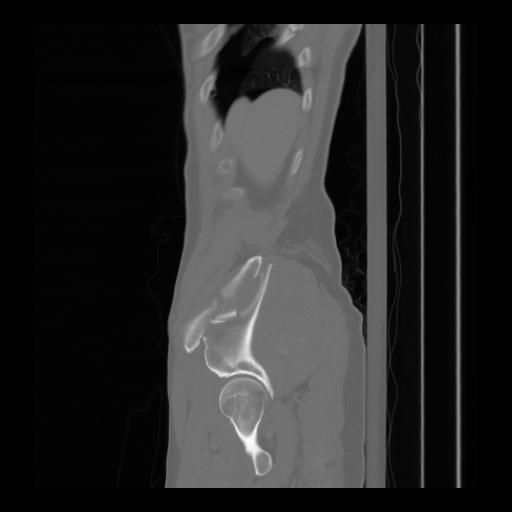

36 CUERPO,CE,Sagittal,3.000,CUERPO,Sagittal,